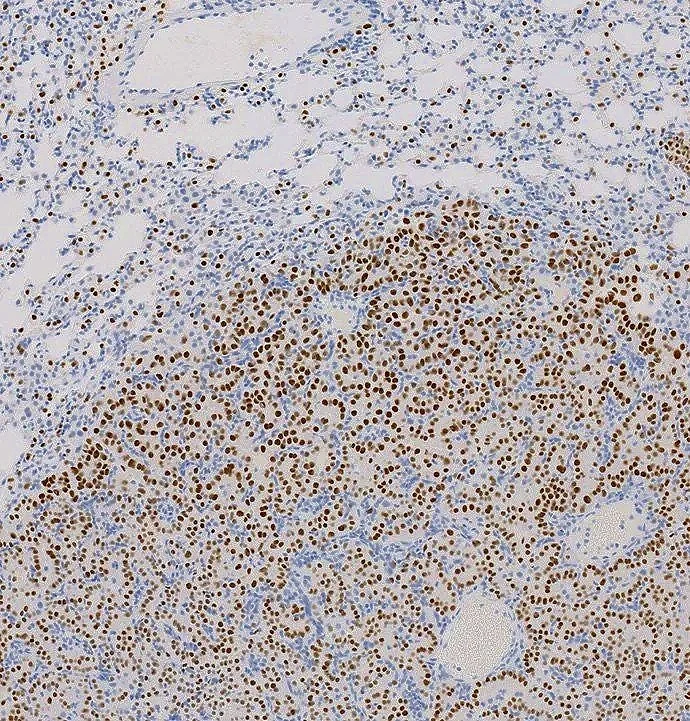

Using a knock-in mouse model that expresses a RIT1 pathogenic variant, we have established mouse models for a rare subtype of lung adenocarcinoma (shown here by µCT and histology) and Noonan syndrome.

For example, we have recently developed mouse models of lung adenocarcinoma and Noonan syndrome driven by mutations in the RAS GTPase RIT1 and have identified therapies that could be used in the clinical setting to treat these conditions.